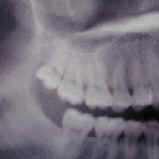

Что касается корневых каналов, то именно здесь и были основные сложности. Оба канала были не слишком здорово обработаны и запломбированы, в результате чего на обоих корнях появились гранулемы.

Но обычный рентгеновский снимок дает плоское 2хмерное изображение, разные структуры накладываются друг на друга, и сложную анатомию каналов на нем не всегда можно разглядеть. Что и произошло в этом случае. Один из каналов имел двойной изгиб. При предыдущем лечении доктор не смог по каким-то причинам этот изгиб увидеть и пройти, уперся в стенки корня, создав т.н. «ступеньку».